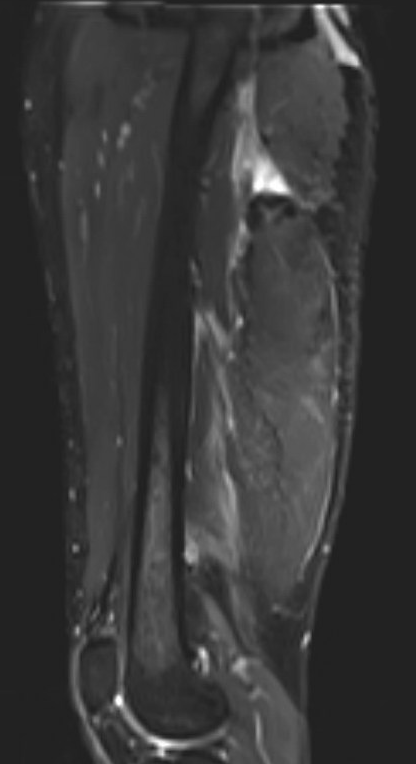

MRI

Proximal hamstring avulsion, with tendon floating in hematoma / seroma

Incomplete tears

High grade partial tear proximal hamstring